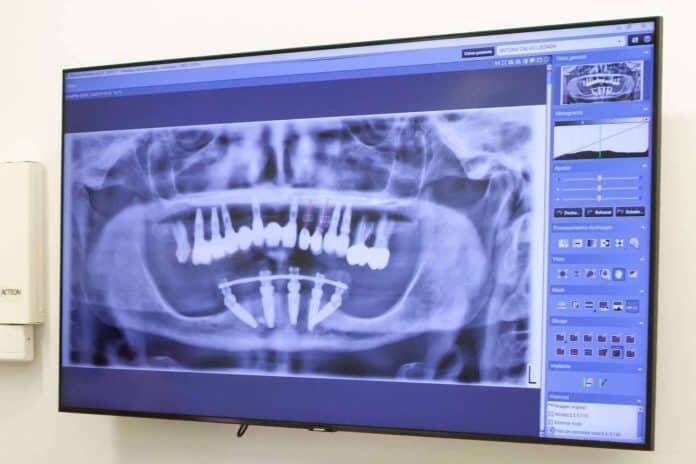

Planificación digital y guías quirúrgicas: La tecnología digital ha revolucionado la implantología. Los escáneres 3D y los programas de planificación permiten una visualización detallada de la anatomía del paciente, lo que facilita la planificación precisa de la cirugía. Las guías quirúrgicas, fabricadas a medida, ayudan a colocar los implantes en la posición exacta planificada, mejorando la precisión y reduciendo el tiempo de cirugía.